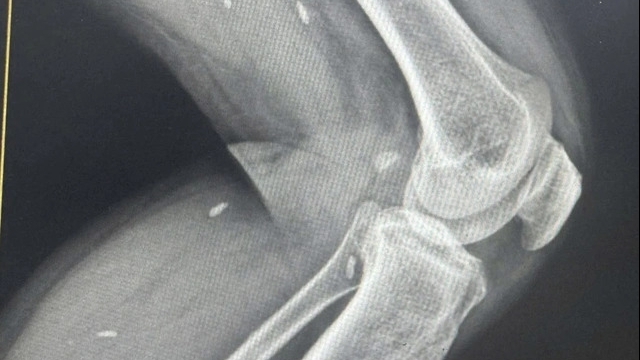

Nguyễn Hồng Ph trước đó được các bác sĩ của Bệnh viện Đà Nẵng nối thành công dương vật bị chính đối tượng cắt trong lúc lên cơn "ngáo đá" tại tòa nhà Luxury Aparment (đườngVõ Nguyên Giáp, phường Phước Mỹ, quận Sơn Trà) vào tối 27/11. Ph từng được đưa đi cai nghiện tập trung tại xã Hòa Bắc, huyện Hòa Vang gần 1 năm nay. Sau khi ra trại vào ngày 25/11 thì Ph tiếp tục lên cơn và quậy phá.